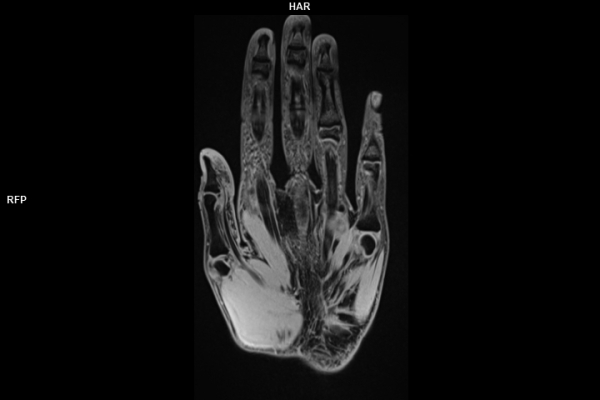

Wir verbinden modernste Medizin mit einer Atmosphäre, in der Sie sich sicher und gut aufgehoben fühlen. Klare Abläufe, Ruhe und Zeit für Sie stehen im Mittelpunkt jeder Untersuchung. CT- und MRT-Bilder ohne Wartezeit. Mit Photon-Counting-CT und 3-Tesla-MRT setzen wir auf in Kärnten einzigartige Technologien für außergewöhnlich detailreiche Bilder und besonders präzise Diagnosen. Die schonenden Verfahren eignen sich auch für Kinder und Jugendliche. Kurze Messzeiten, große offene Geräte und ein ruhiges Umfeld sorgen für eine angenehme Untersuchung und ein gutes Gefühl von Anfang bis Ende.

• Muskuloskelettale Bildgebung

• Neuroradiologie

Wir bieten ein breites Spektrum an Untersuchungen an, von Standarduntersuchungen der Gelenke, Organe oder großflächigen Körperregionen bis zu Spezialuntersuchungen zum Beispiel des Herzen oder der Gefäße. Zusätzlich werden Angiographien (Darstellung von Blutgefäßen), Endometriose-Abklärungen und Mamma-Untersuchungen durchgeführt. Genauere Details können Sie der MRT/CT-Übersicht und der Preisliste entnehmen, oder Sie wenden sich direkt an unser Team, das Sie gerne zur passenden Untersuchung berät.